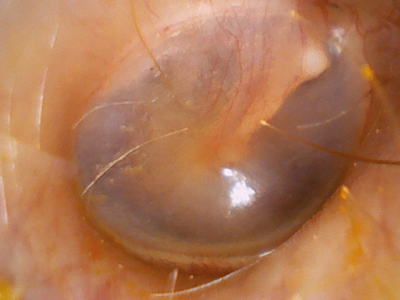

Syncvision iO1 OTO - otoscopy image.

Syncvision - iO1 OTO **BEST TESTED**

Type: Complete system Captures images only

Cost: £780 (incl. shipping + tax)

Image quality: 85%

Field of view: 93%

Ease of use: 93%

Comments: Excellent image quality, and very easy to use. The Syncvision is designed to be held vertically, although holding it horizontally as for an otoscope feels more natural. Very quick to set up and use, and the capture is button conveniently placed. Has the advantage of not requiring any additional equipment.